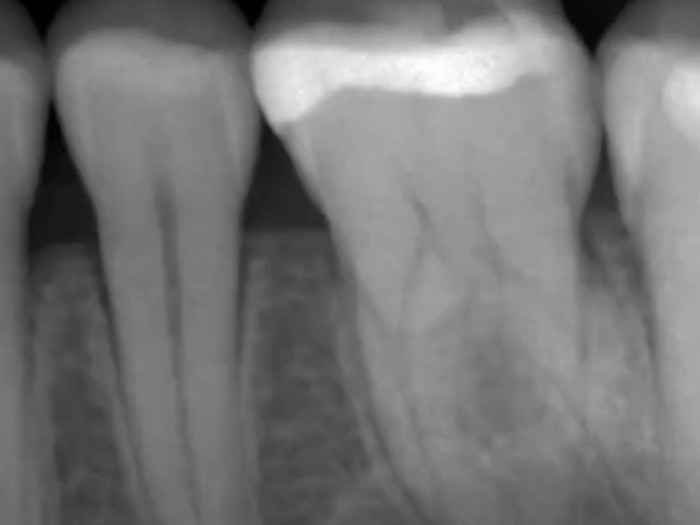

Die DIAGNOcam Vision Full HD verwendet für diesen Prozess Nah-Infrarot-Beleuchtung (NIR) anstelle von weißem Licht. Auf den Produktfotos können Sie sehen, das zwei kleine Arme am Gerät zu sein scheinen. Diese Arme werden über den Zahn geführt, um ihn von der bukkalen und lingualen Seite zu umschließen, und sie enthalten Glasfasern, die das NIR-Licht von beiden Seiten des Zielzahns abgeben. NIR dringt unschädlich und effektiver in den Zahn ein als weißes Licht und ohne Lichtverschmutzung. Diese Bilder sind genauso klar wie die intraoralen Bilder und können dem Patienten zur Erläuterung der Befunde vorgelegt werden.

Die Transillumination ist ein großartiges Instrument zum Auffinden von Läsionen, die zu klein sind, um auf Röntgenbildern erkannt zu werden. Sie ist ein hervorragendes Hilfsmittel für die Frühdiagnose, die Kinderheilkunde und schwangere Patienten. Sie ist auch ein hervorragendes Instrument zur Überwachung der Remineralisierungstherapie.

Die Transillumination ist auch ein nützliches Instrument zur Lokalisierung von Rissen in Zähnen und Karies unter Versiegelungen und Restaurationen. Für konservative Ärzte ist dieses Produkt eine wunderbare Ergänzung für ihre Patienten.